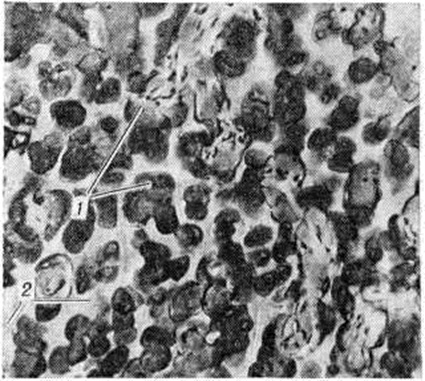

При микроскопическом исследовании обнаруживается, что патологический избыточное костеобразование идёт во всех костях скелета как в области эпифизарного хряща (ростковой зоны), так и по ходу диафиза. Очень редко наблюдается периостальное костеобразование. В костномозговых пространствах в некоторых случаях обнаруживают толстые слоистые структуры, располагающиеся вокруг капилляров и представляющие собой патологический остеоны. В других случаях костномозговые пространства бывают выполнены пластинчатой костной тканью с многочисленными дугообразными линиями склеивания. Встречаются балки из незрелой грубоволокнистой костной ткани. В пластинчатой кости уменьшено количество остеобластов, распределение их в костной ткани неравномерное. Явлений резорбции кости почти не наблюдается. Костномозговые пространства резко сужены, выполнены фиброретикулярной тканью. Лишь местами можно встретить участки костного мозга. В зоне энхондрального окостенения основная субстанция хряща не подвергается резорбции, как это имеет место в физиологический условиях, а даёт образование костной ткани, сначала в виде округлых островков (рисунок 1), а затем широких костных перекладин, по краям которых видны остатки основной субстанции хряща. По мере удаления от эпифизарного хряща вещество кости приобретает пластинчатое строение (рисунок 2).